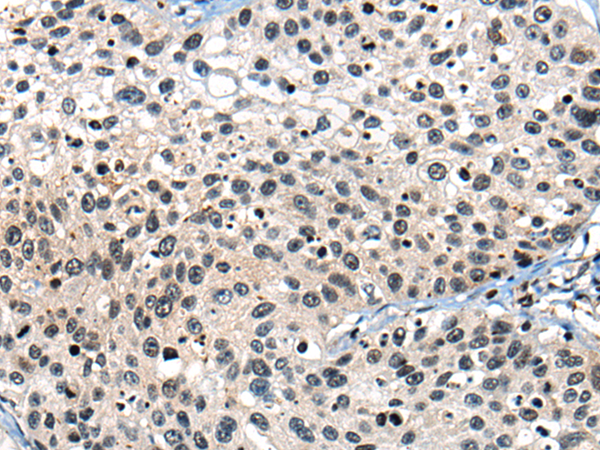

分类: 科研抗体货号: P06210别名:应用: WB,IHC反应种属: Human, Mouse, Rat